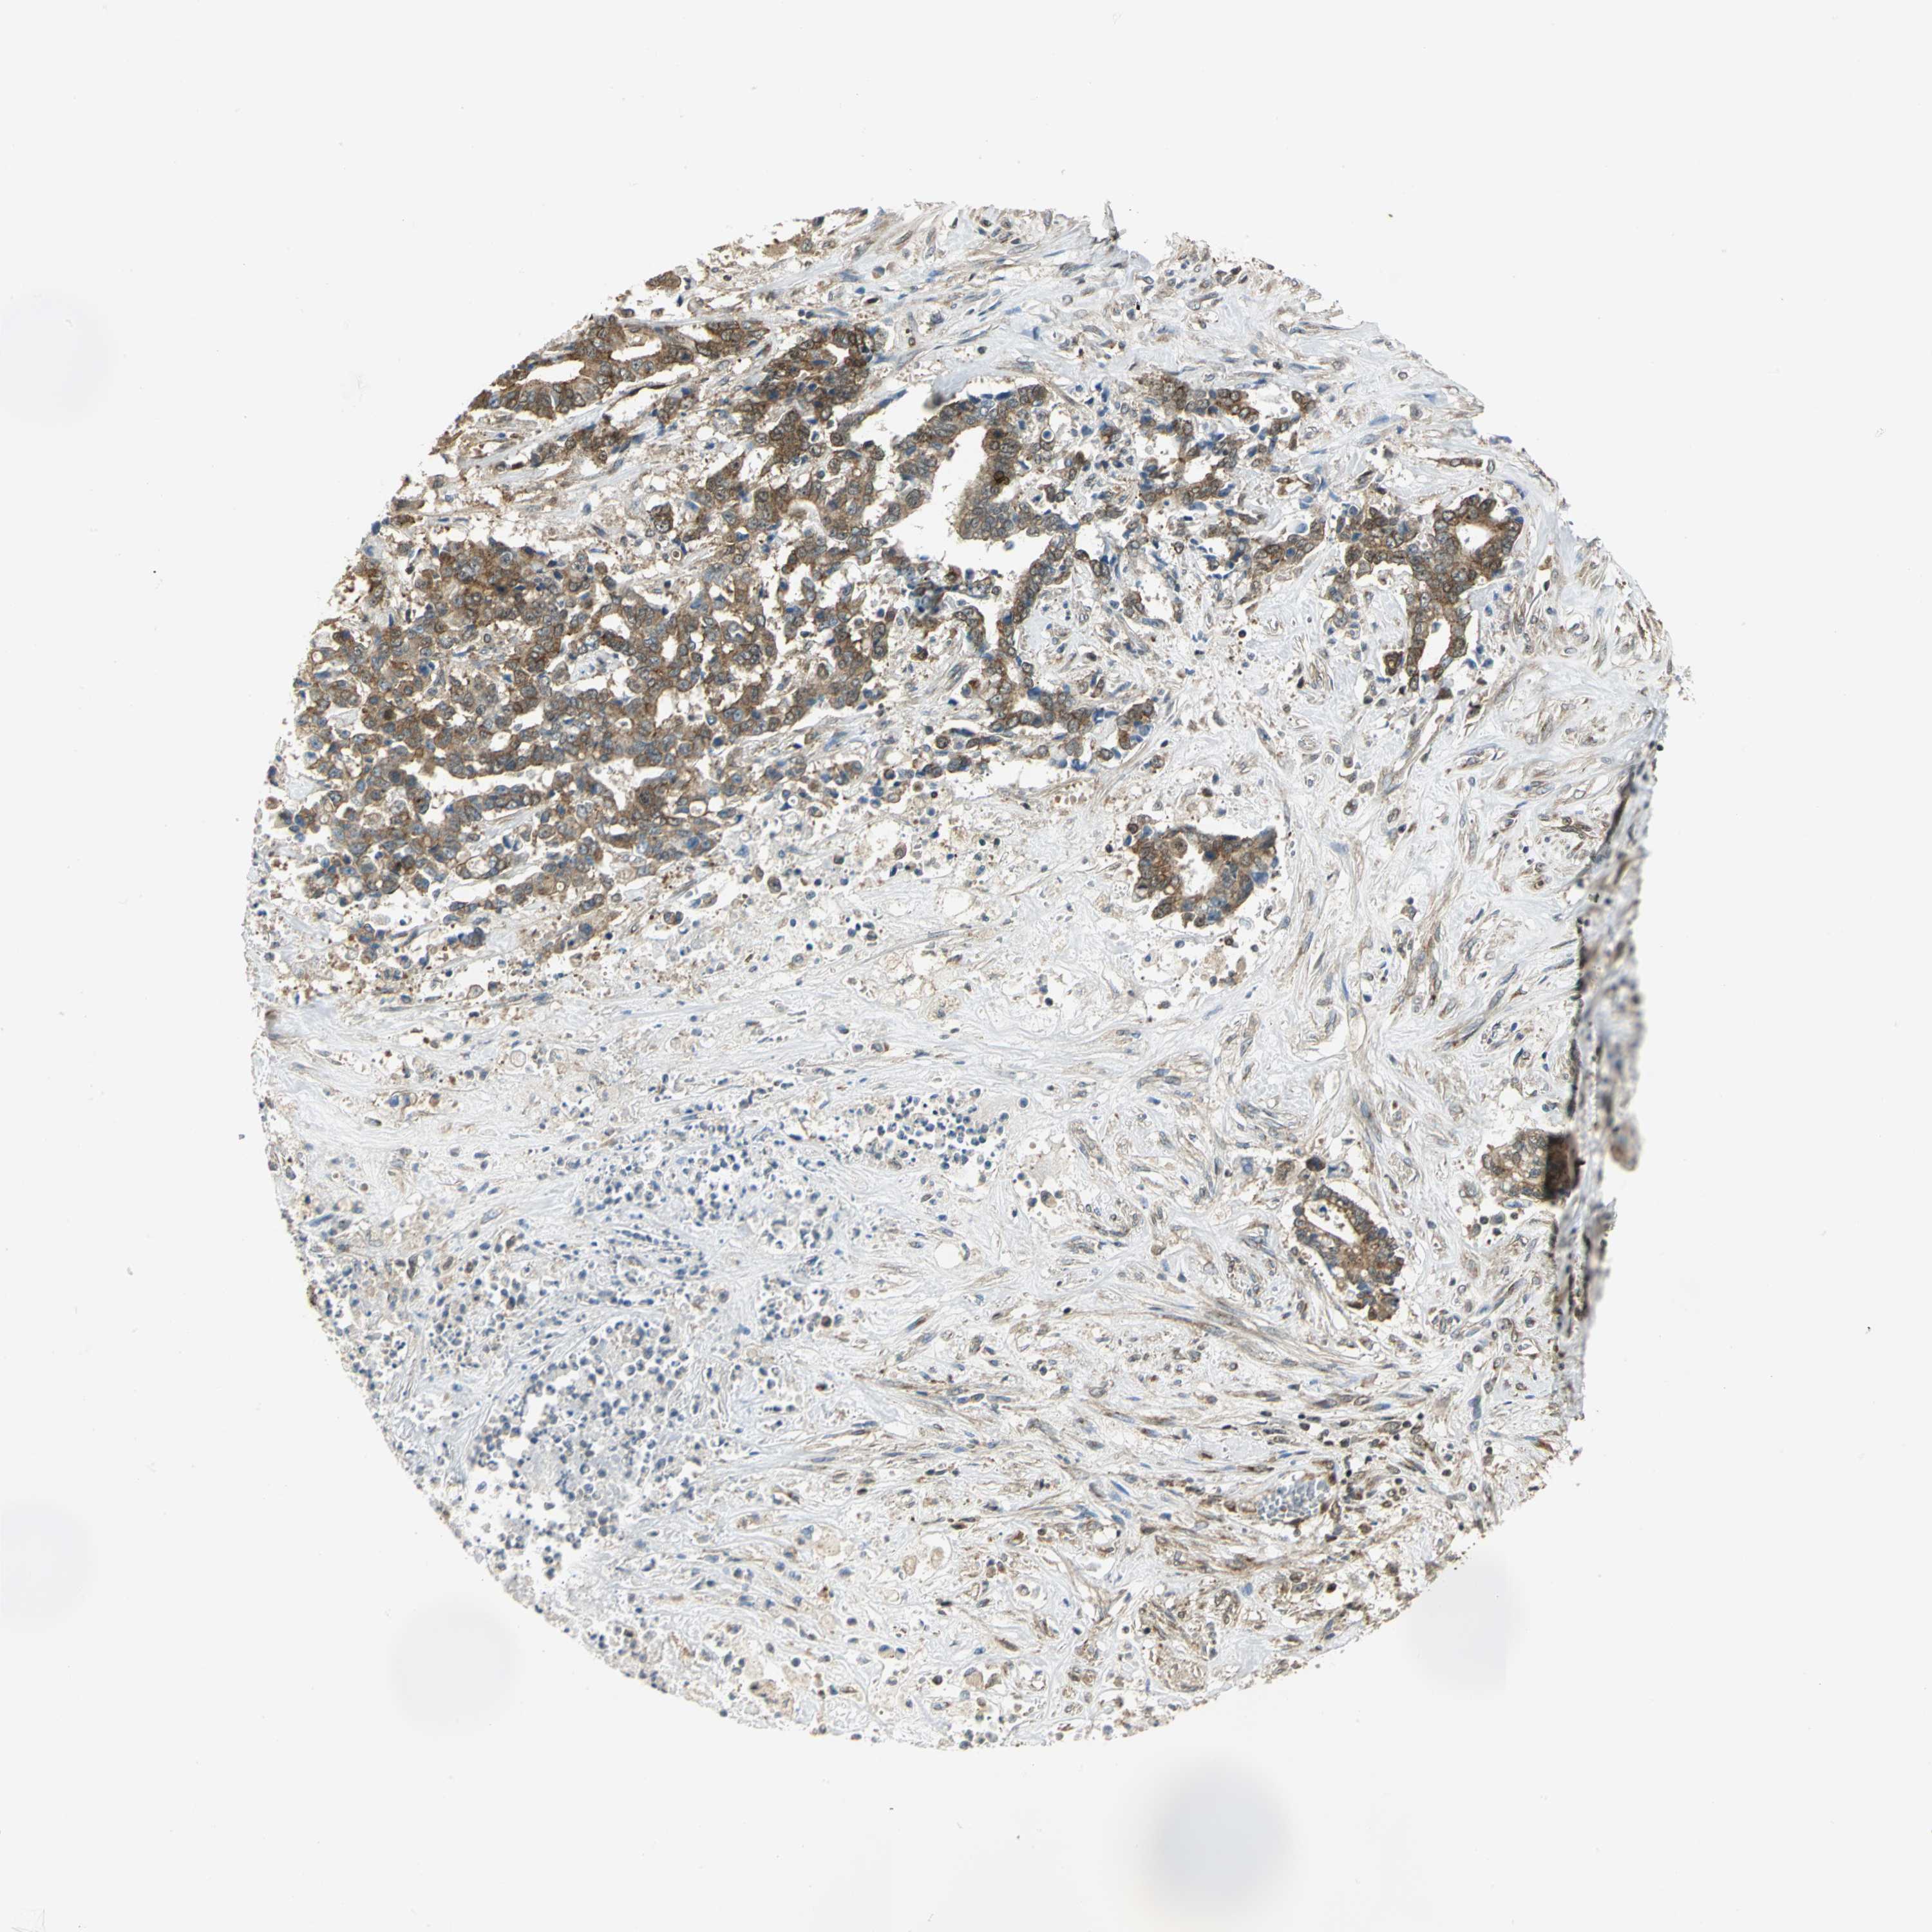

LIVER CANCER - Protein expressioni

A mouse-over function shows sample information and annotation data. Click on an image to view it in a full screen mode. Samples can be filtered based on level of antibody staining by selecting one or several of the following categories: high, medium, low and not detected. The assay and annotation is described here.

Note that samples used for immunohistochemistry by the Human Protein Atlas do not correspond to samples in the TCGA dataset.

Antibody stainingi

Antibody staining in the annotated cell types in the current human tissue is reported as not detected, low, medium, or high, based on conventional immunohistochemistry profiling in selected tissues. This score is based on the combination of the staining intensity and fraction of stained cells.

Each image is clickable and will lead to virtual microscopy that enables deeper exploration of all samples and also displays staining intensity scores, fraction scores and subcellular localization as well as patient and tissue information for each sample.

Antibody HPA020043

Antibody CAB005868

Staining

High

Medium

Low

Not detected

Intensity

Strong

Moderate

Weak

Negative

Quantity

>75%

75%-25%

<25%

None

Location

Nuclear

Cytoplasmic/membranous

Cytoplasmic/membranous,nuclear

Carcinoma, Hepatocellular, NOS

Cholangiocarcinoma